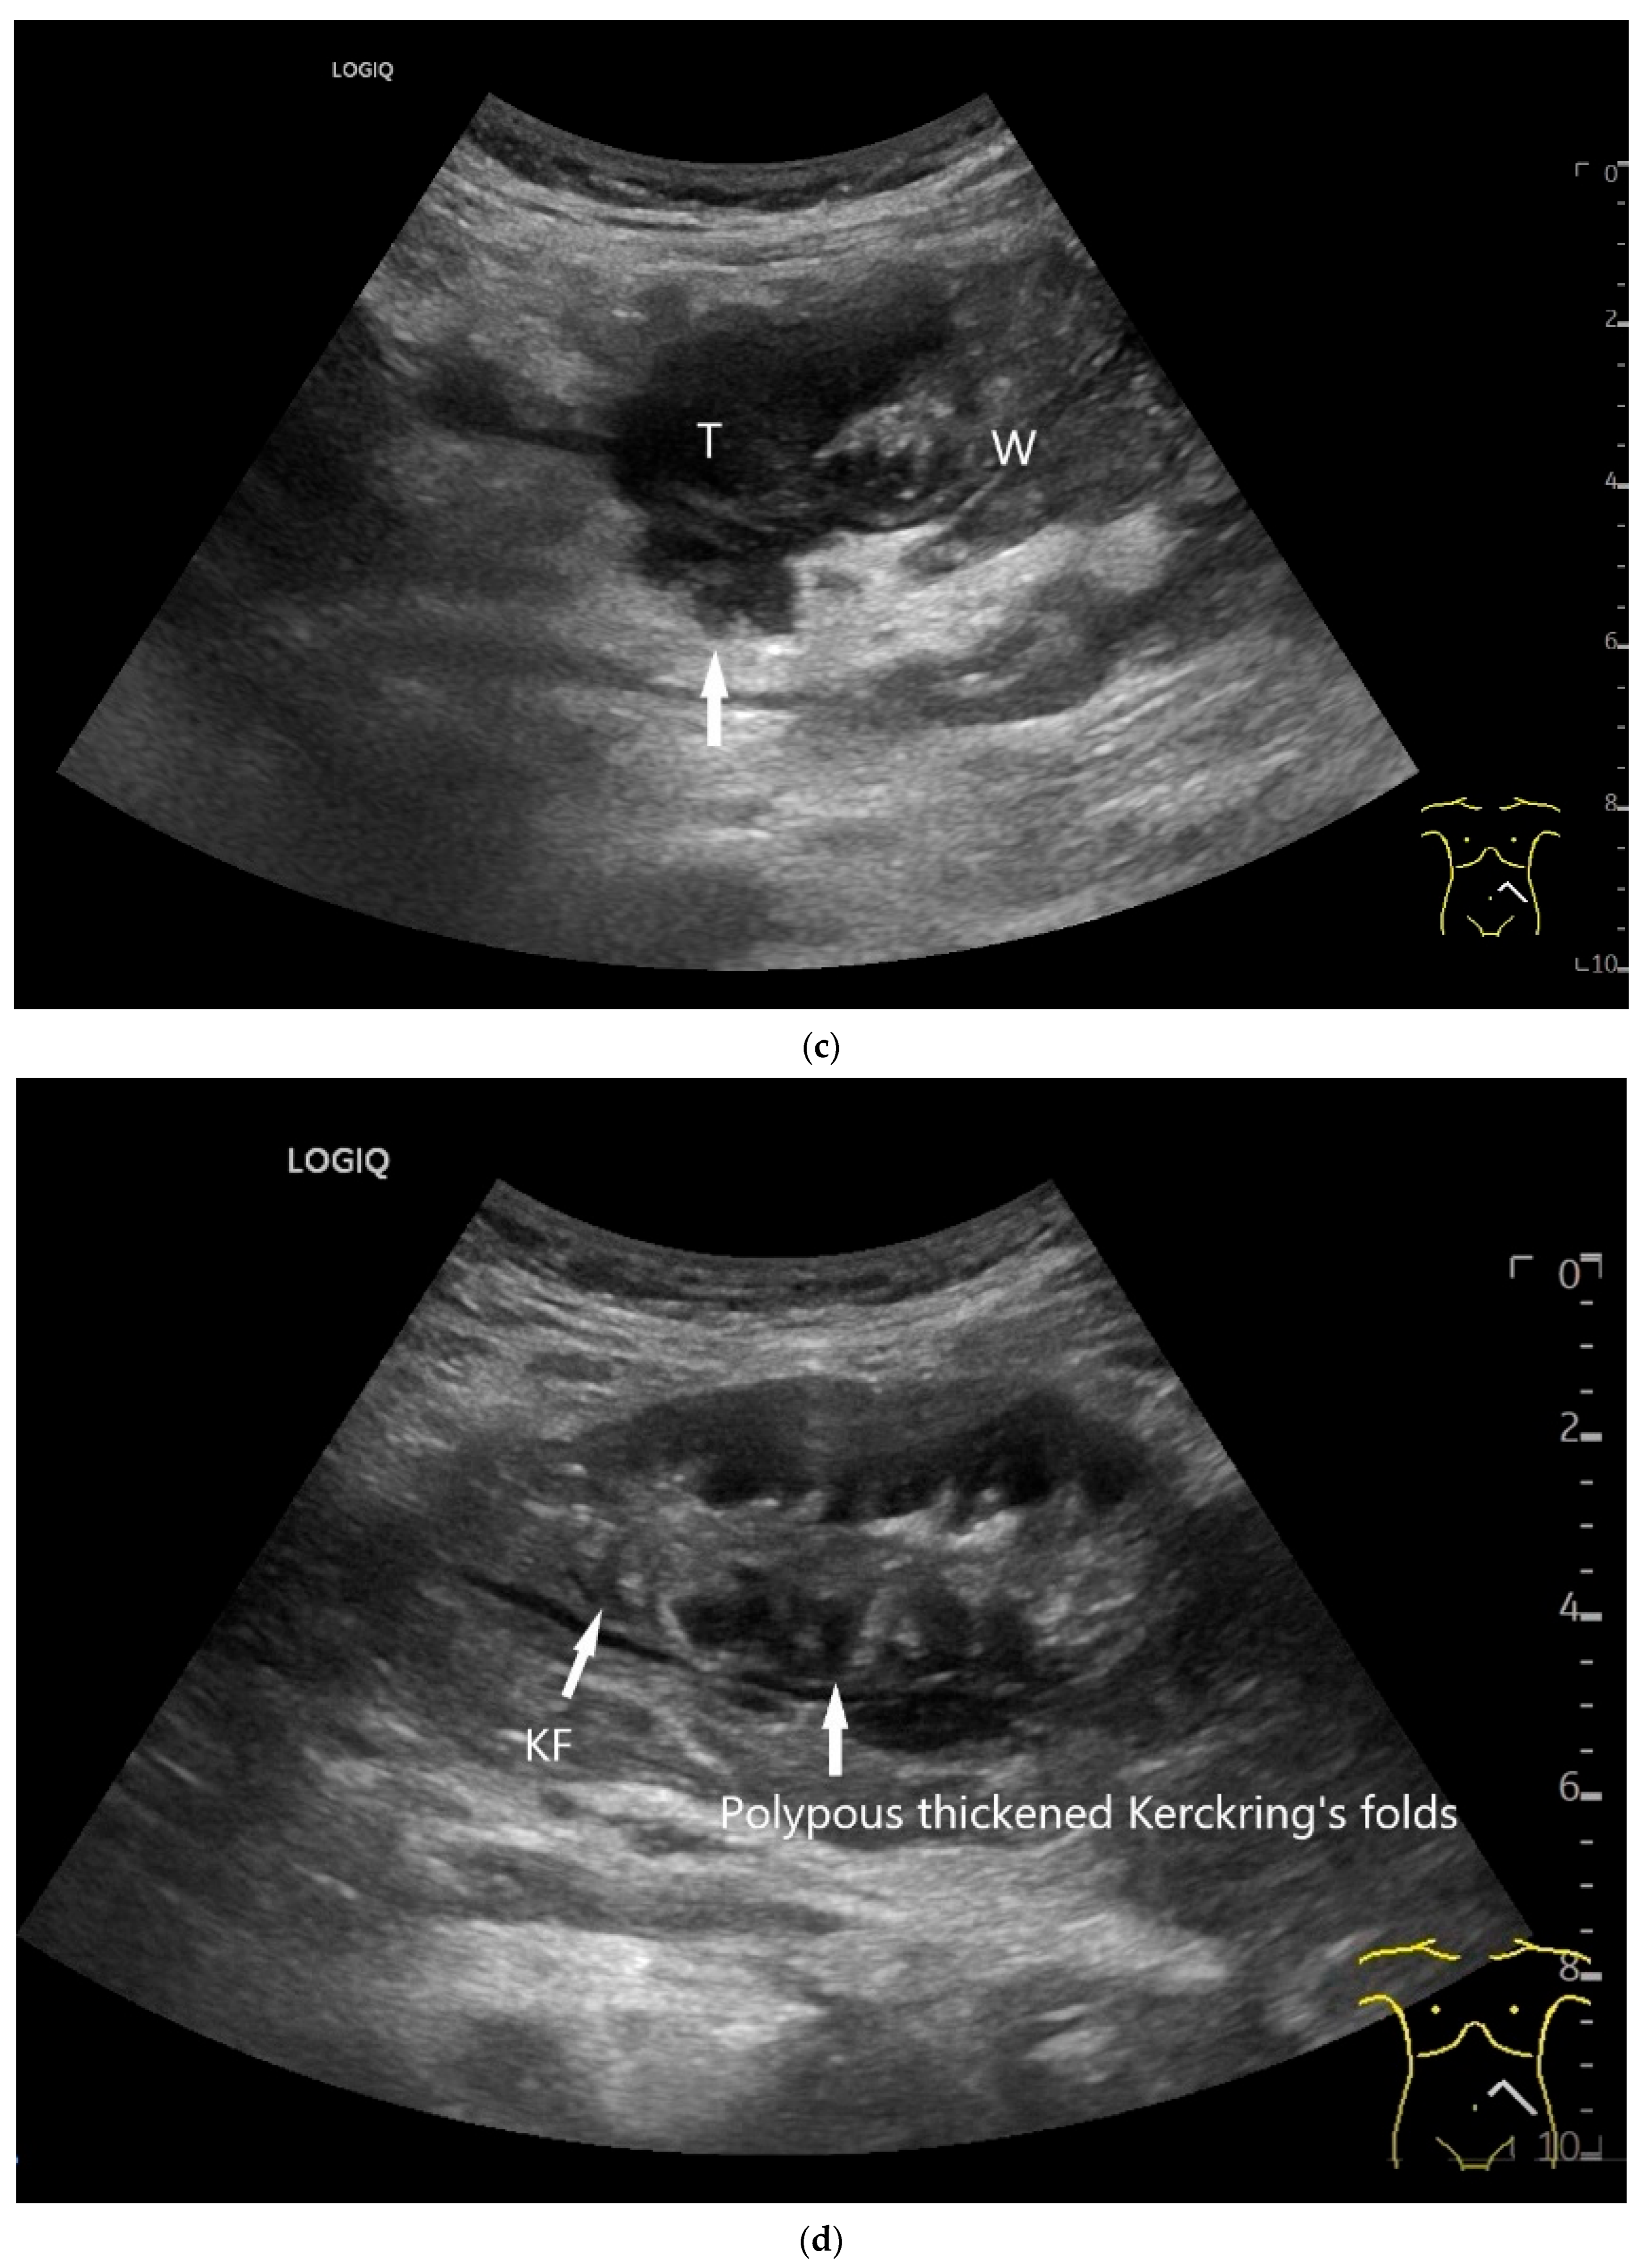

- Smereczyński, A.; Starzyńska, T.; Kołaczyk, K. Mesenteric changes in an ultrasound examination can facilitate the diagnosis of neuroendocrine tumors of the small intestine. J. Ultrason. 2015, 15, 274–282. [Google Scholar] [CrossRef]

| Neuroendocrine tumor | Small, nodular hypoechoic wall thickenings, mostly in the submucosa with spreading into the other layers. Usually with small vessels on CDI. Regionally enlarged lymph nodes. Multilocular manifestations are possible. |